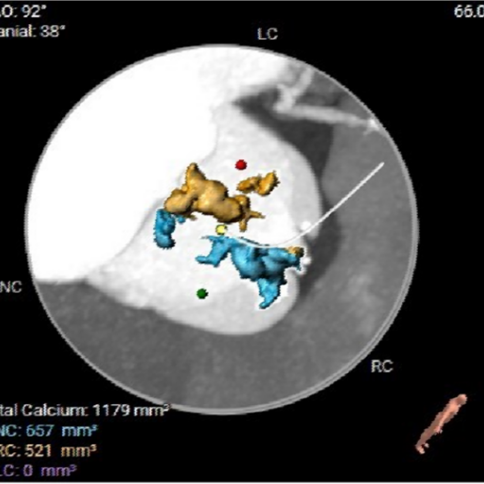

· Type 0型二叶式主动脉瓣,左右冠脉不同窦,重度钙化,钙化分布较均匀,左冠窦和无冠窦内钙化呈块状主要分布在对合缘及瓣叶边缘,瓣叶对合缘存在局部钙化粘连及纤维增厚;

HU850